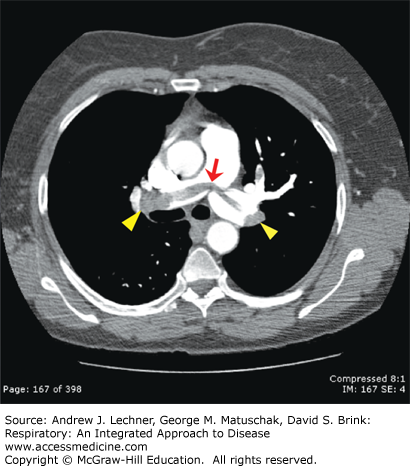

Contrast CT angiogram of the chest showing a "saddle" pulmonary embolism (red arrow) as well as filling defects in the left and right pulmonary artery branches (yellow arrowheads) secondary to obstruction by thromboembolic materials. Read more in Respiratory: An Integrated Approach to Disease, Chapter 15.